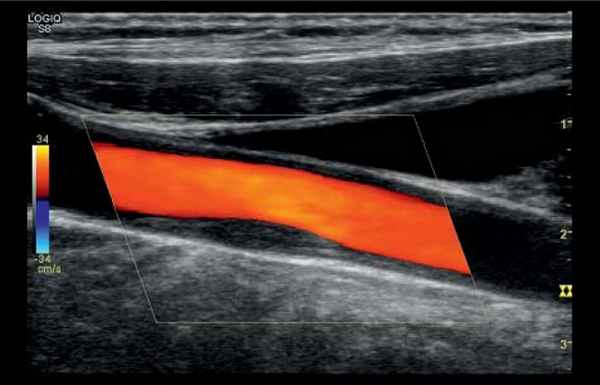

УЗИ сосудов брюшной полости проводится на аппарате экспертного класса GE Logiq S8 с применением режима B-flow, который помогает качественно оценить состояние сосудов.

Режим цветового картирования позволяет лучше увидеть объемную картинку расположения сосудов, оценить мелкие и расположенные глубоко сосуды. Допплерогафия позволяет оценить характер кровотока в сосуде, степень сужения сосуда, влияние стеноза на кровоток. Исследуется как артериальное, так и венозное кровообращение.

Клиника ЭКСПЕРТ оснащена высококлассным оборудованием, что имеет ключевое значение для точной оценки необходимых параметров сосудов. Для качественного исследования сосудов используется наиболее современный режим B-flow, визуализирующий кровоток в реальном времени. Эта методика позволяет врачу “увидеть” стенки сосуда, наличие тромба или атеросклеротической бляшки.

Визуализация сосуда в режиме B-Flow